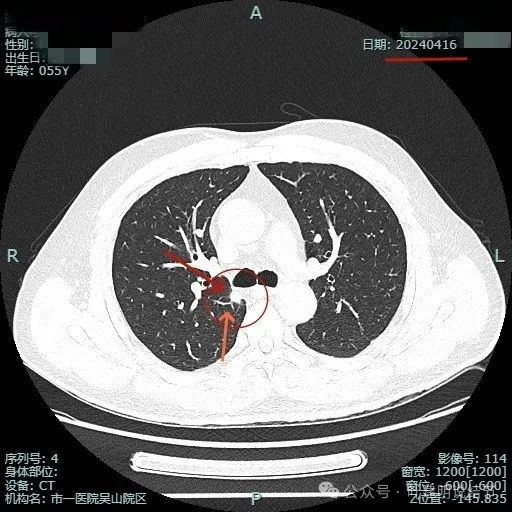

我们先来看2024年4月的病灶影像:

病灶出现,位于右上叶靠近肺门侧,此层显得像磨玻璃密度,轮廓较清。

其实应该实性密度的,前面层面应该是较为边缘部位的关系。病灶表面有点毛糙。

结节毛刺明显,而且是细毛刺。

有微血管走向病灶,结节与纵隔侧紧贴,但胸膜牵拉不明显。

有明显血管征,而且进入的血管是弯曲改变走行的。

表面不平显毛糙,有细毛刺。

此层显得病灶缺乏膨胀性,边缘较为平直。

边缘区较淡,也显得有点散。

病灶没有钙化。